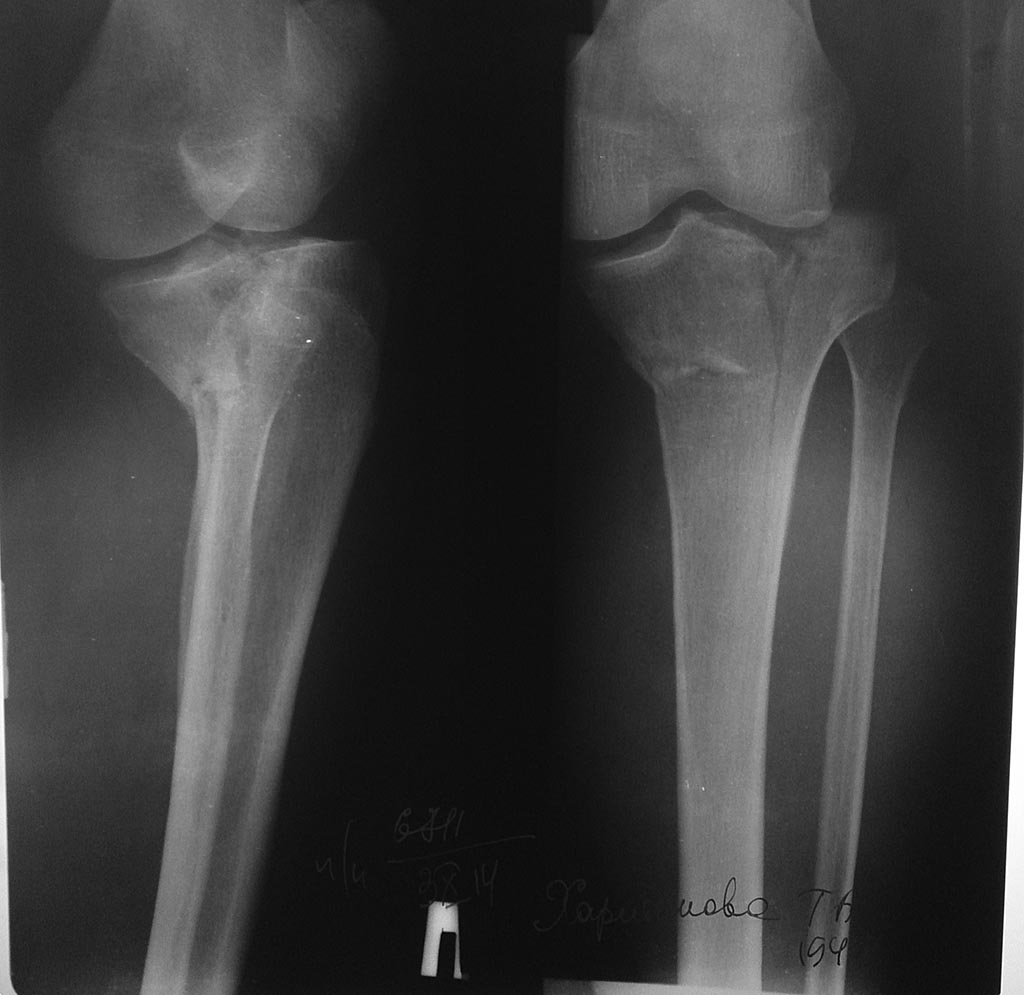

[Ortho] перелом медиального мыщелка большеберцовой кости

Доброго времени суток! Прошу совета. Женщена 66 лет упала с подножки 5

дней назад. Состояние мягких тканей удовлетворительное. Соматически не

отягощена. Посоветуйте, пожалуйста, чем оперировать и из какого доступа.

По КТ изолированный перелом мыщелка(часть латерального целая)